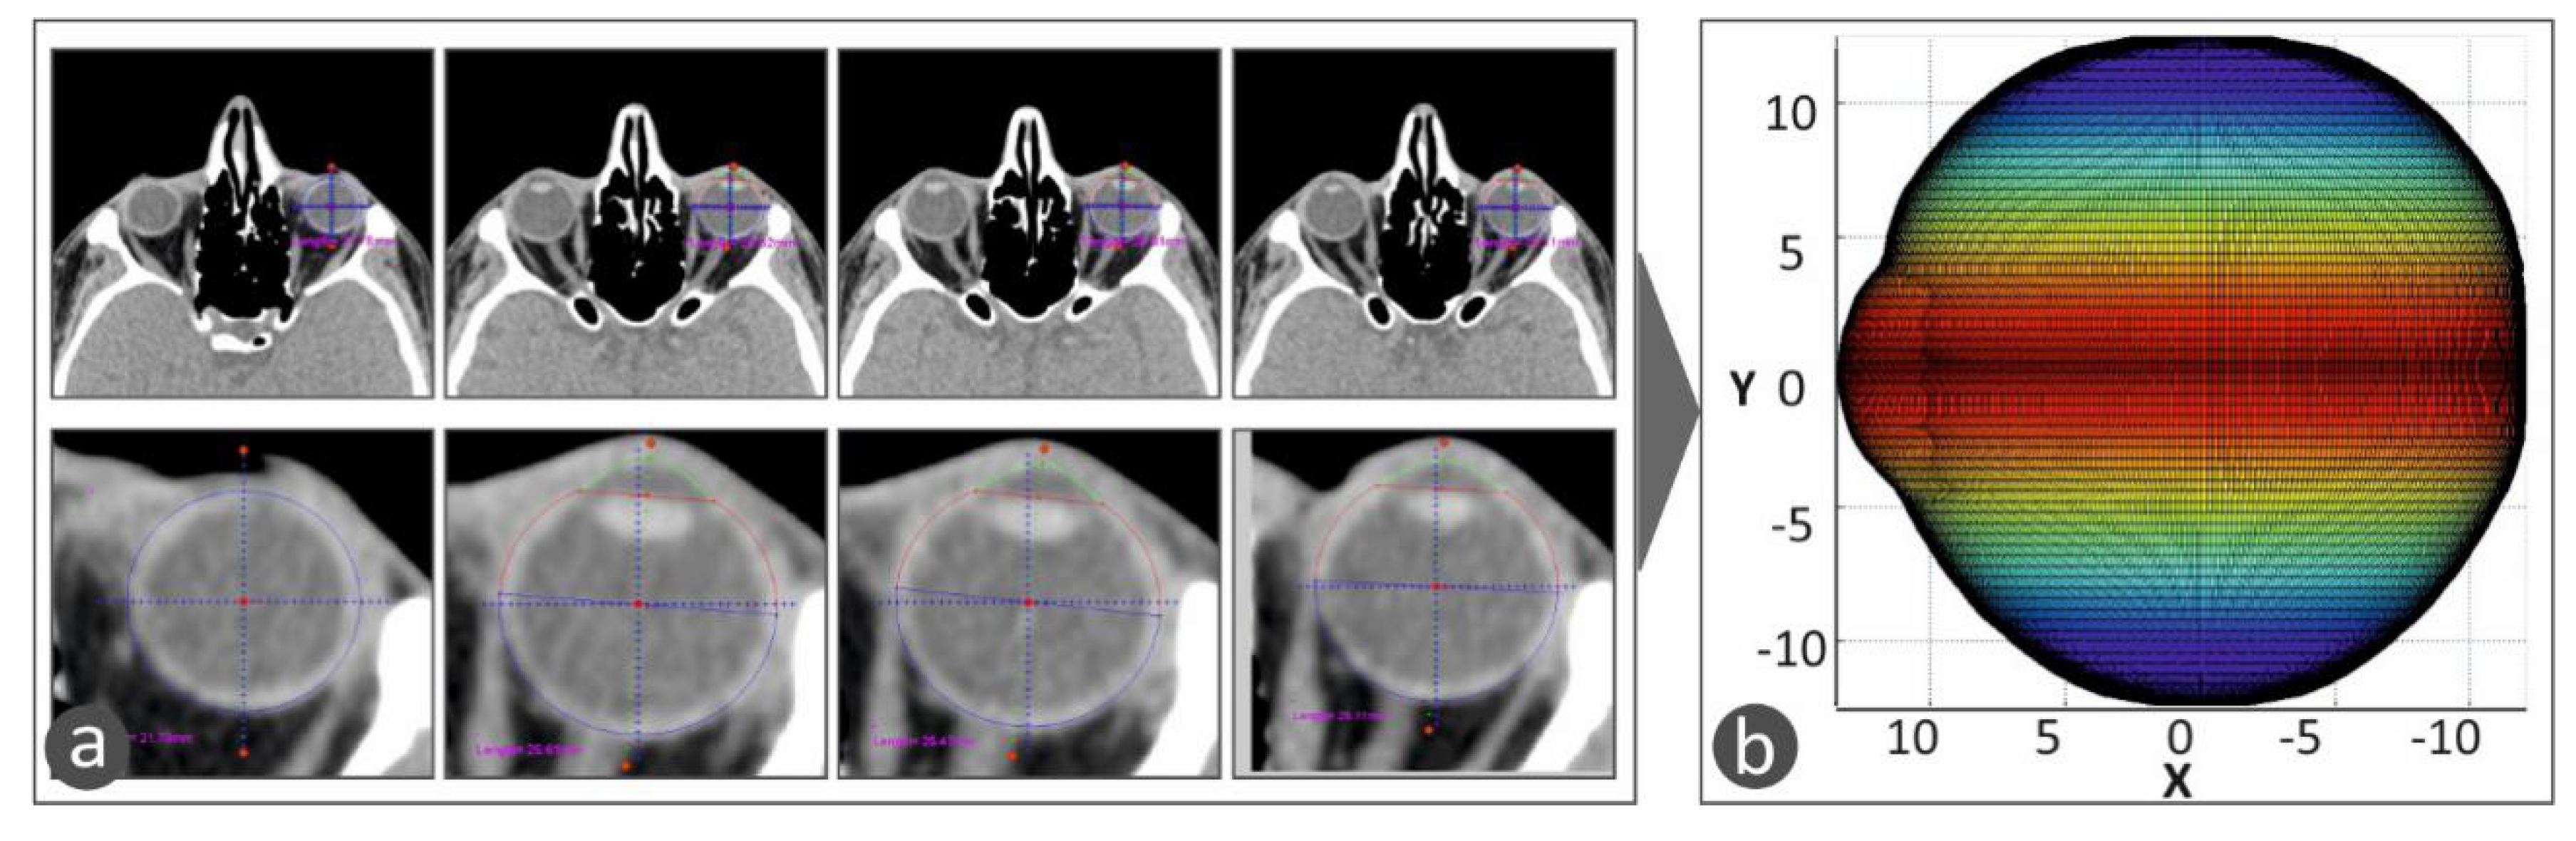

These algorithms were developed, and the CT images were processed in the Matlab Student software (Mathworks, MA, USA), which provides integrated tools and flexibility in reading and editing the tomography images. All the CT images were scanned, one by one, and the perimeter of the specific eye was acquired from each slice. The algorithm considers any movement of the patient or the patient’s eye during the scan in order to avoid developing distorted geometric models during the procedure to capture the human anatomy of each patient. Taking into consideration the slice thickness, the space between slices, and the pixel spacing, a three-dimensional geometric model of the eye was developed. The three-dimensional representation of the eye shows the iris and the quadrants of the eye. This representation of the 3D geometry helps the operator position the macular buckle accurately (Figure 3). Figure 3a shows typical CT images, in which the perimeter of the eye is determined and acquired for the determination of the 3D geometry of the eye. Figure 3b shows the 3D geometric model determined from the CT scan images and represented with a color scale. The color scale at this face of the work was used in the vertical direction to show the human eye height vs. the change in the human eye section size in the horizontal direction.

Figure 3.

The 3D model of the human eye in the developed software. A color scale was used in the vertical direction to show the human eye height vs. the change in the human eye section size in the horizontal direction: (a) CT scan images in which the perimeter of the eye is determined and acquired, (b) 3D geometric model of the eye determined from the CT scan images and represented with a color scale